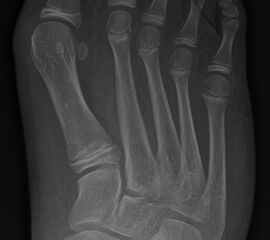

In der Regel bestehen aktive Wachstumsfugen bei Mädchen bis zum 12. und bei Jungen bis zum 14. Lebensjahr, mit Abweichungen von einem Jahr nach unten und nach oben. Präzise Informationen unter anderem darüber gibt das präoperative Röntgenbild (Abb. 2).

Abb. 2 a-c: offene Wachstumsfugen MT I Basis und Zehen (a), teilweise geöffnete Wachstumsfugen (b) und geschlossene Wachstumsfugen (c).

Zum Lesen der Bildbeschreibung und zur Vollansicht bitte die Bilder anklicken. Bilder: A. Helmers.